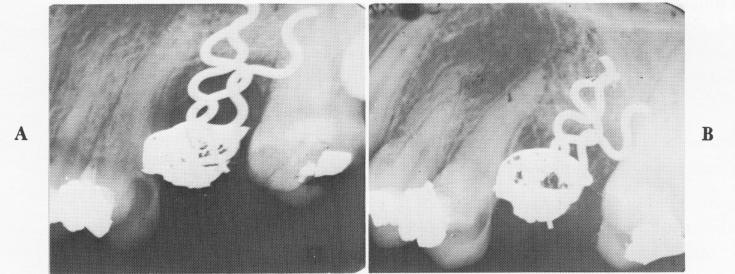

Fig. 8-84. A, An immediate postoperative radiograph of the pins inserted into the open socket and fastened together inside the crown with acrylic. B, A 14-month postoperative radiograph shows the fill-in of bone.

Some specially designed implants have been suggested, such as Linkow's twisted pins, shown in Fig.

8-83. These are bent during the intervention to fit the socket and their ends driven into holes and crevices specially drilled for them. Although they may work (Fig. 8-84), the unstandardized, off-the-cuff insertion procedures invite mistakes.